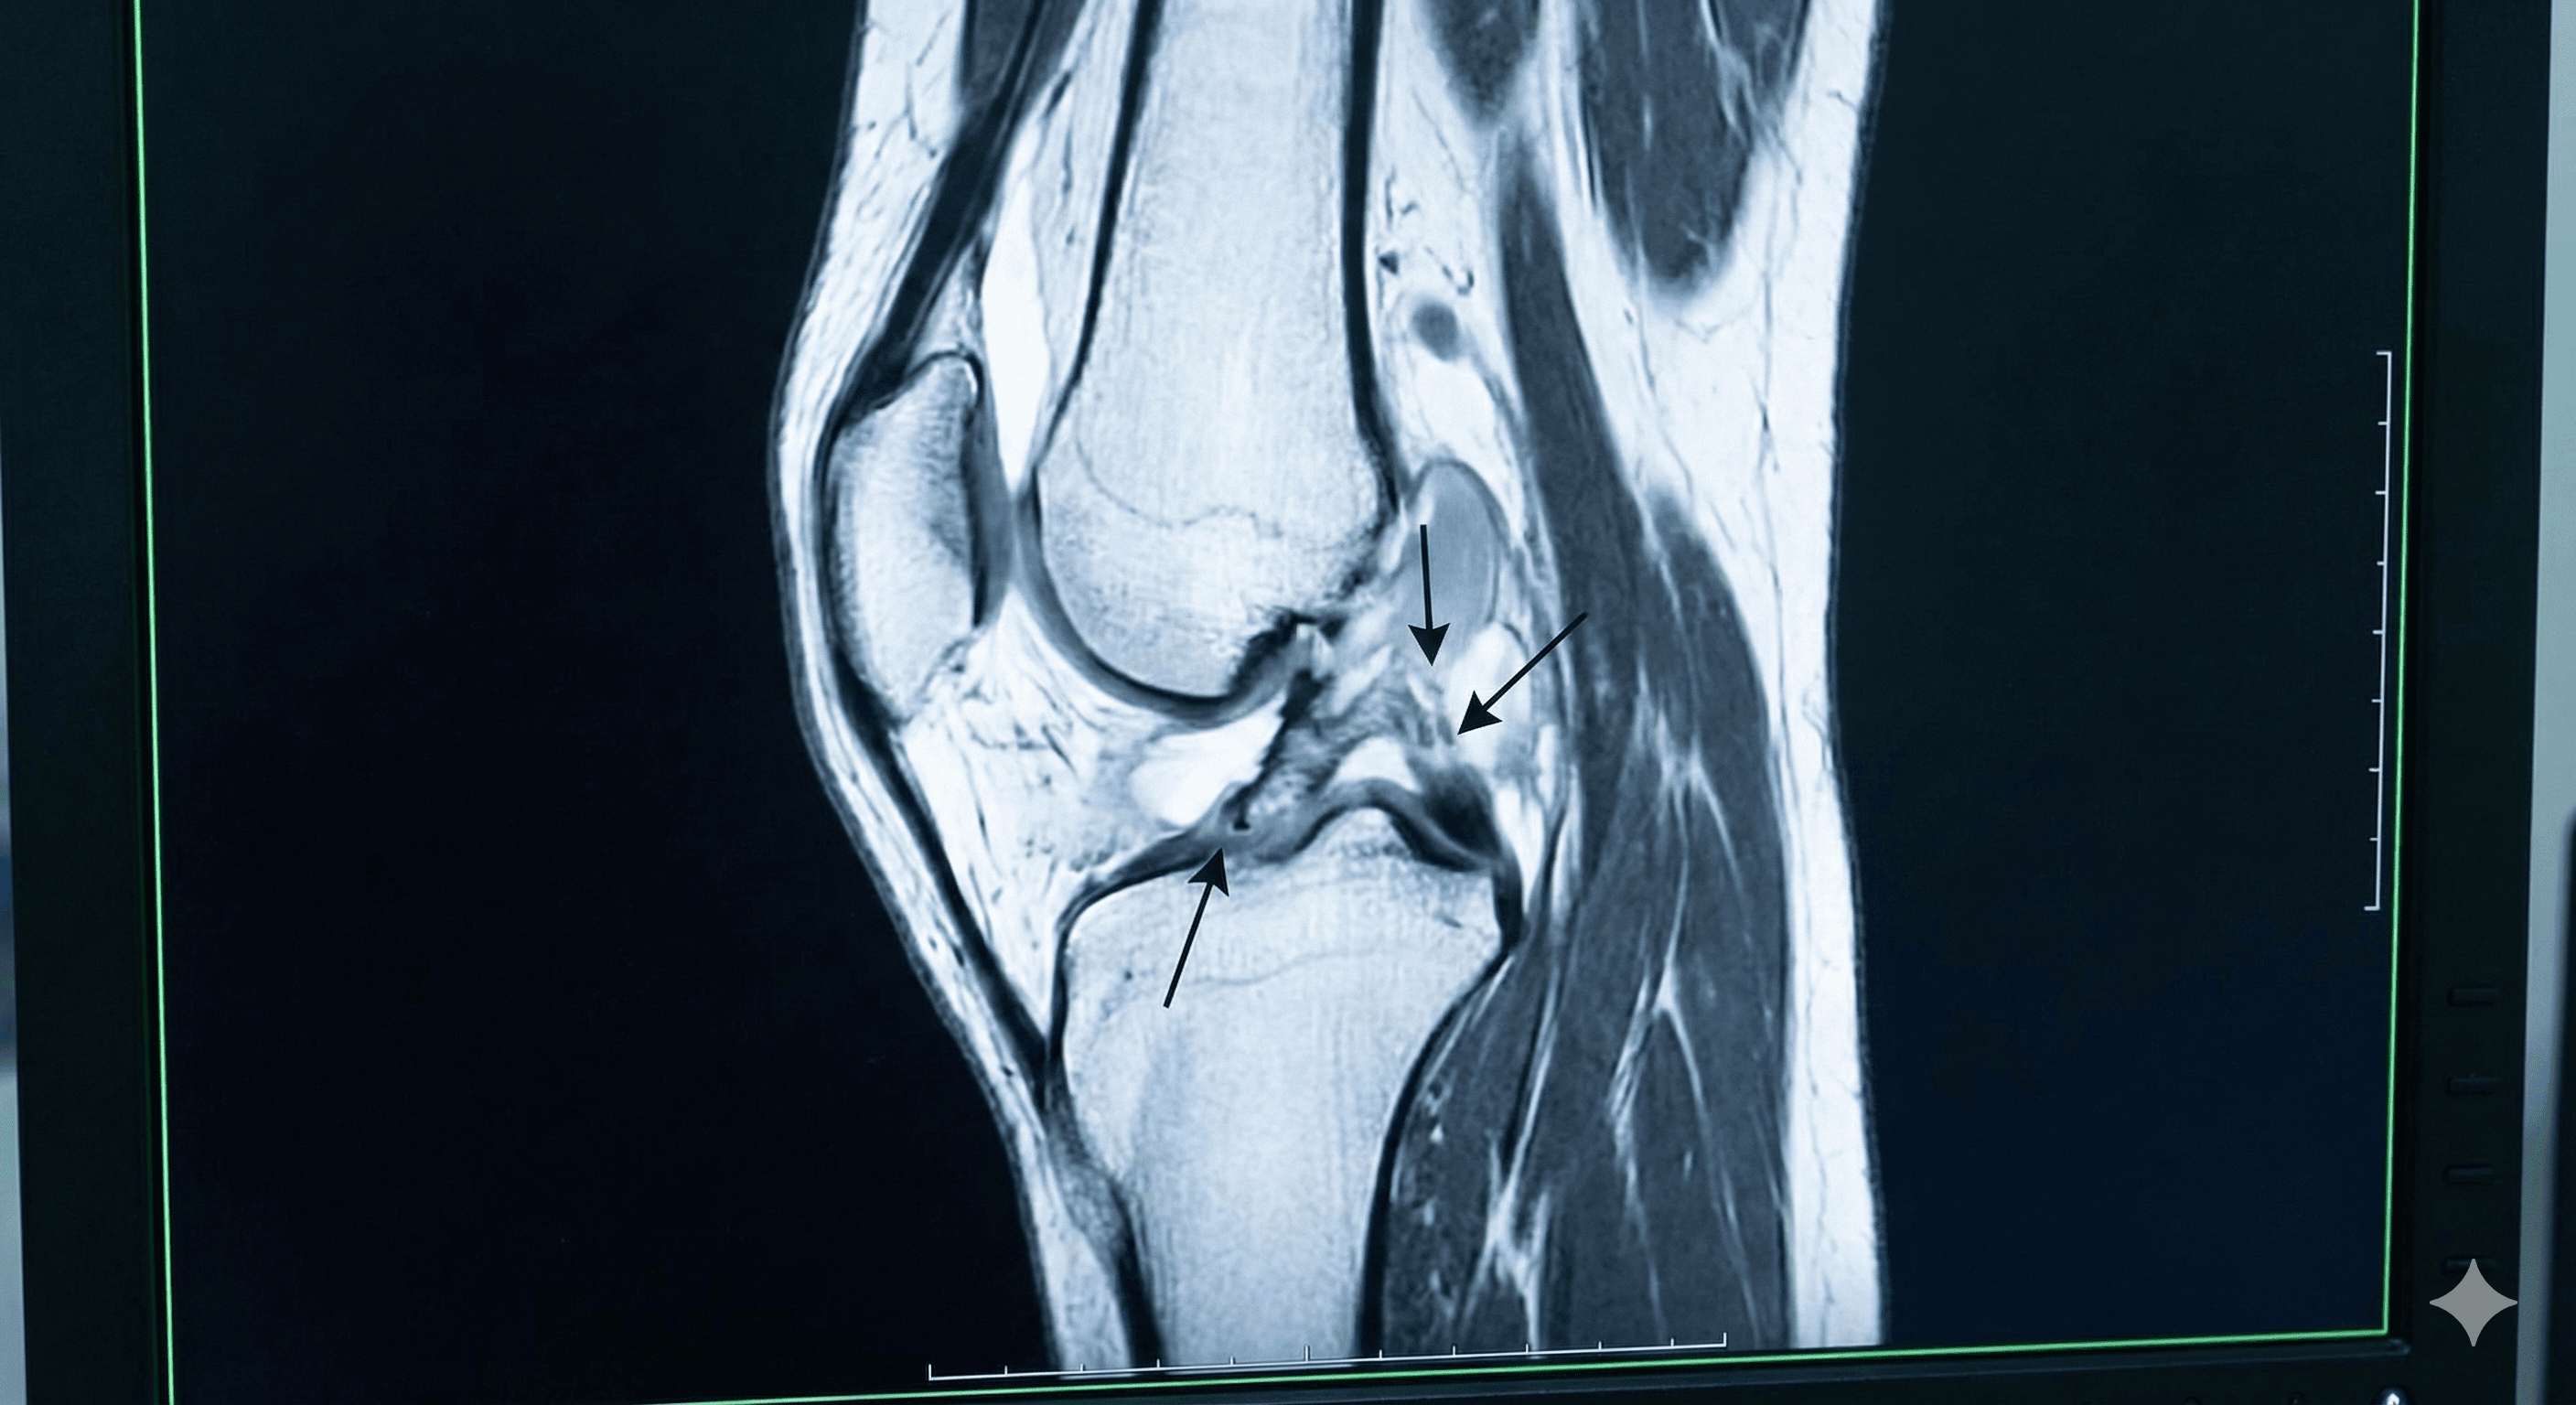

Desgarro del ligamento que estabiliza la rodilla, común en deportistas tras giros bruscos o caídas.